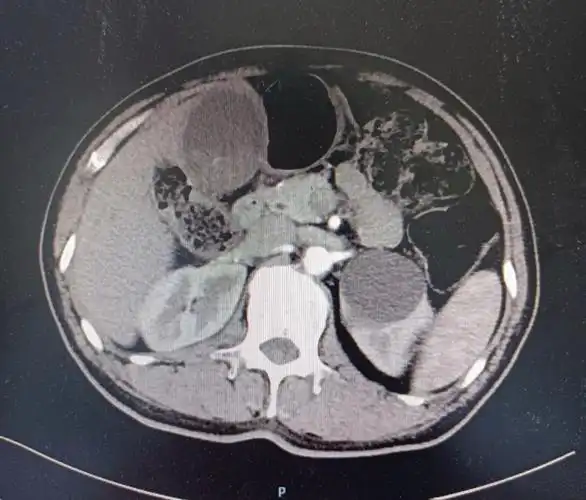

男63胆囊炎胆结石致梗阻性黄疸什么叫mirizzi请检阅

ct提示胆囊结石伴胆囊炎